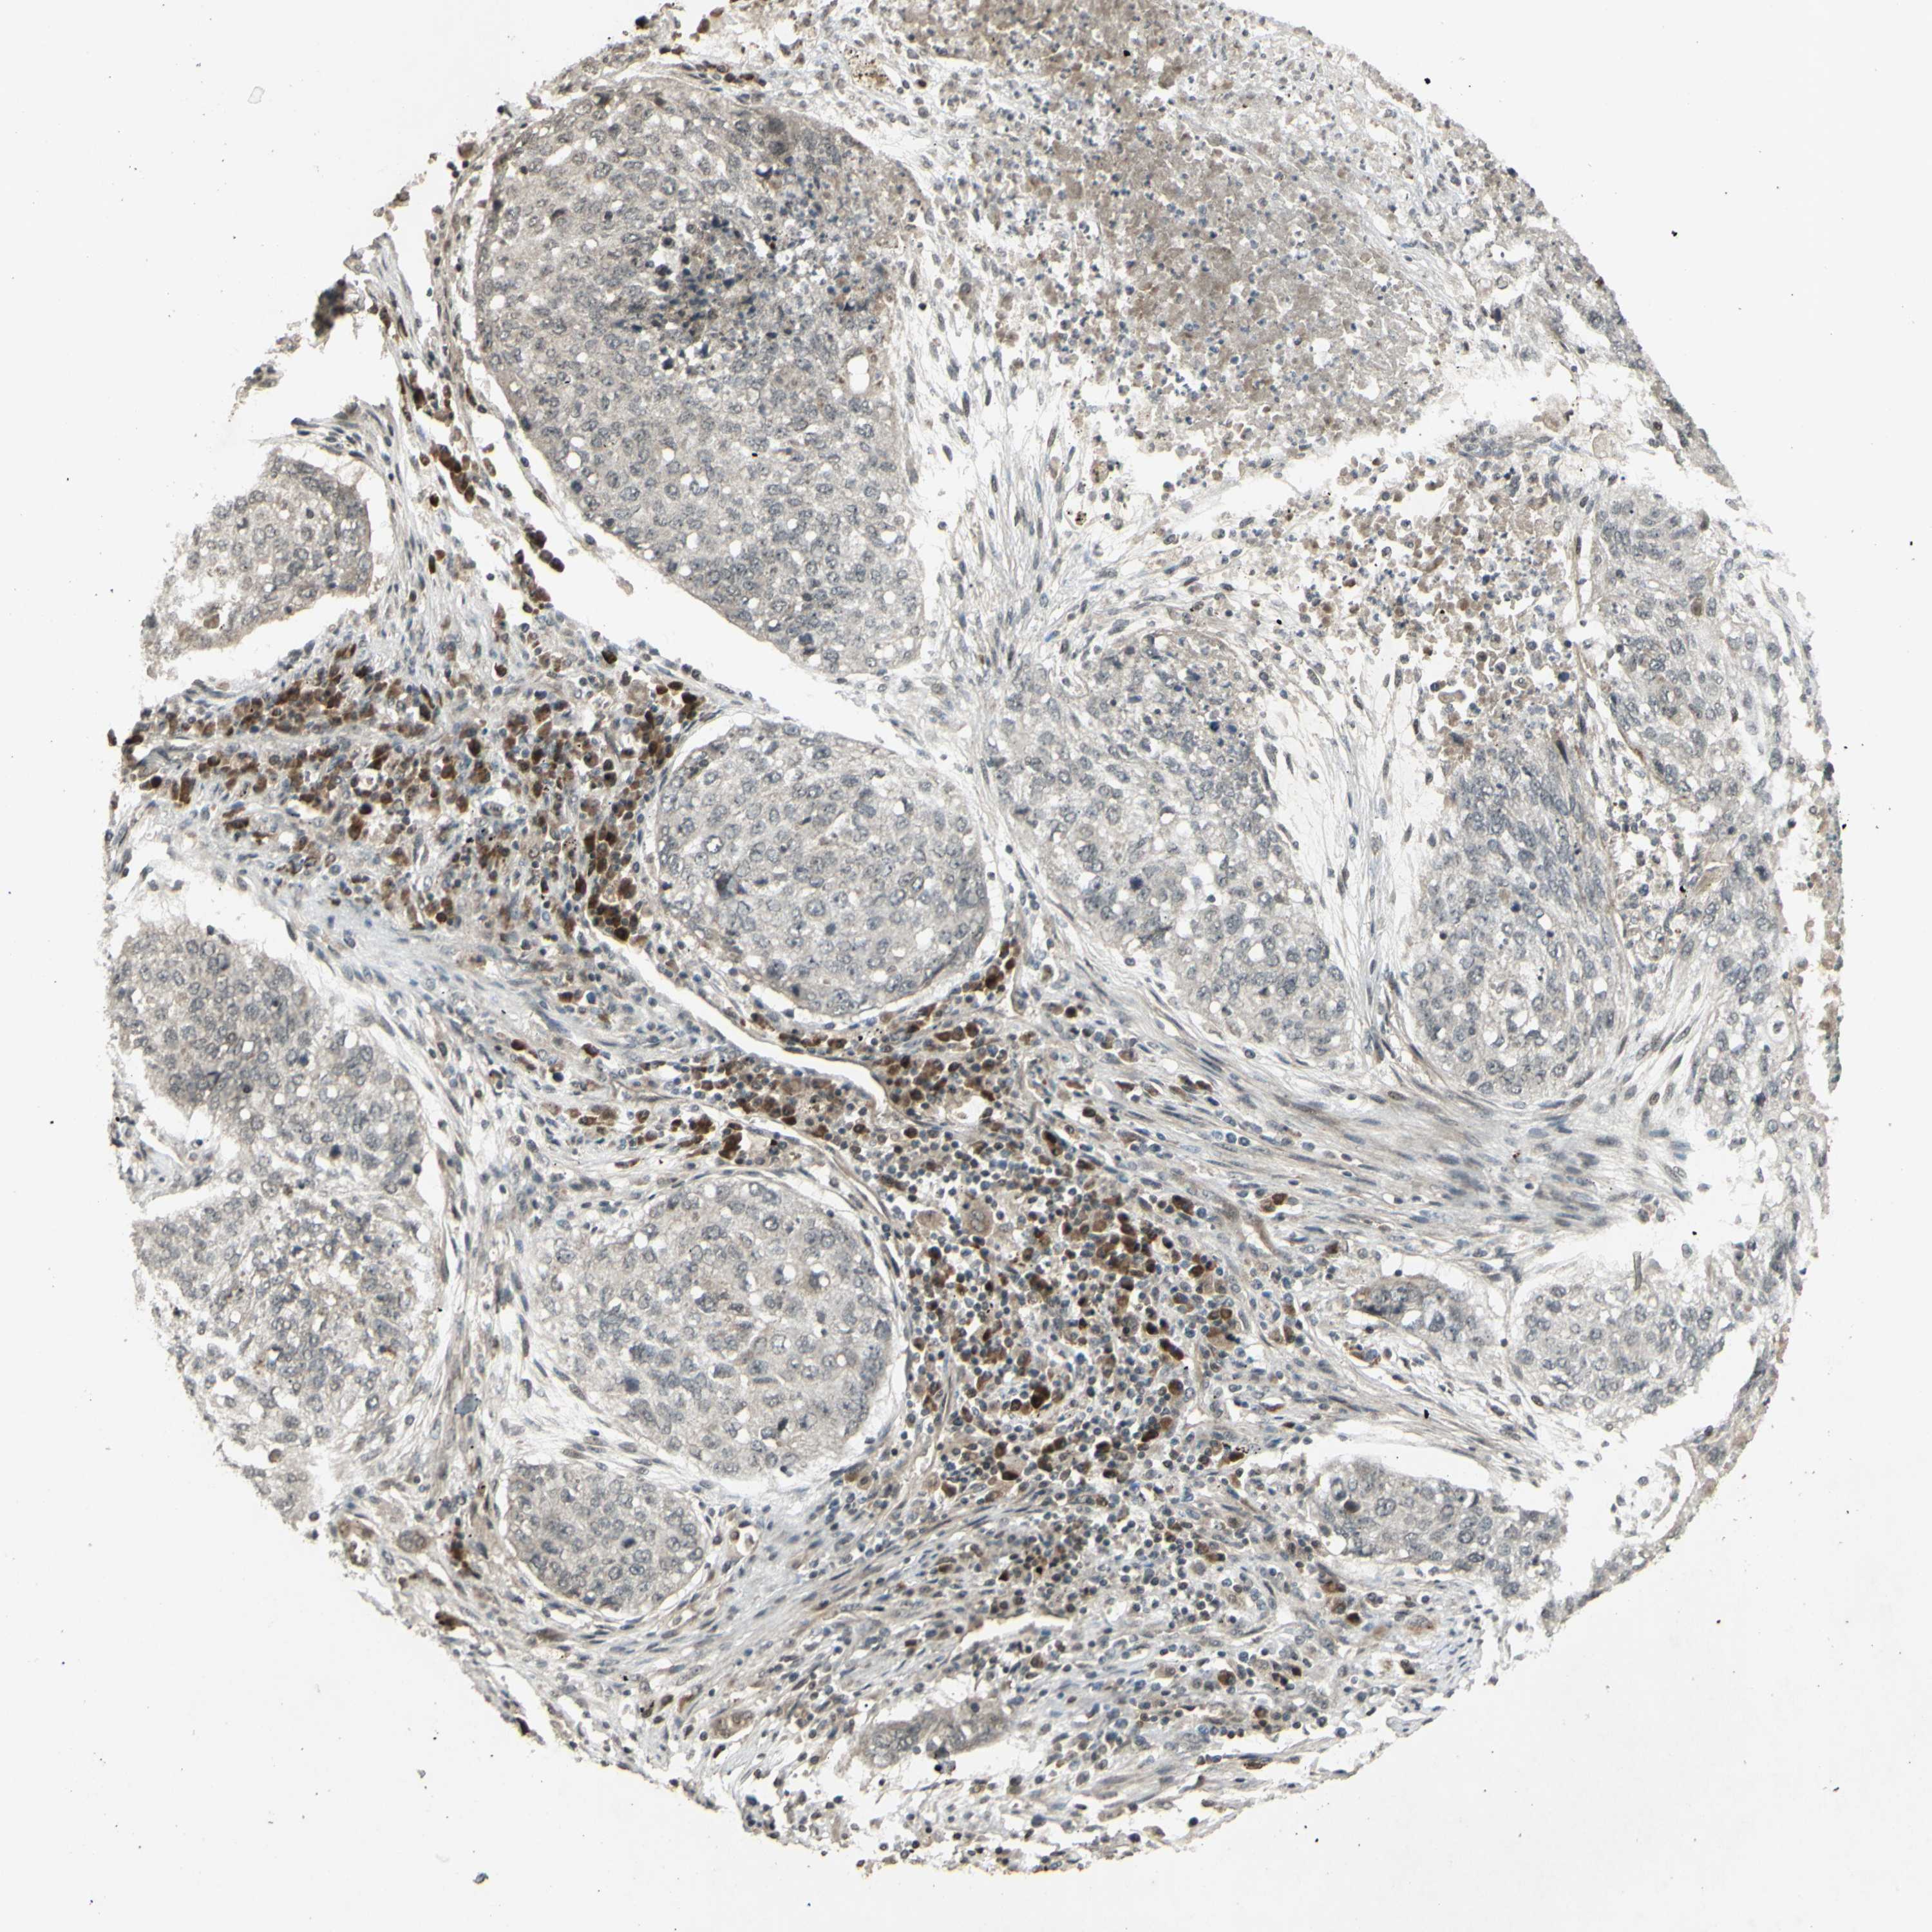

CANCER LUNG CANCER Show tissue menu

LUAD TCGA LUAD VALIDATION LUSC TCGA LUSC VALIDATION PROTEIN LUAD CPTAC PROTEIN LUSC CPTAC PROTEIN EXPRESSION